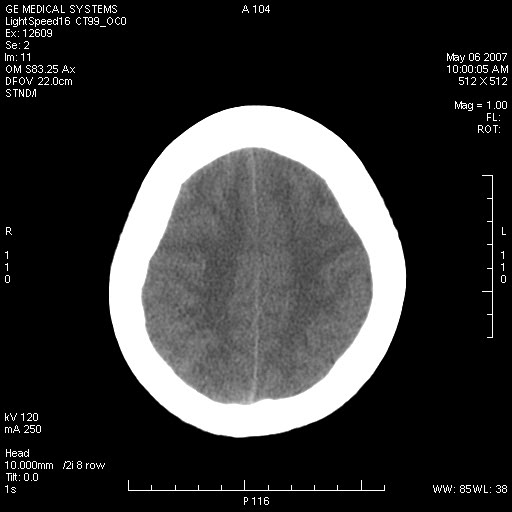

女,60岁,头痛6~7天。

右颞叶巨大高低混杂密度肿块,病灶内可见多发条块状钙化影,占位效应明显,中线结构显著左偏,肿块周围水肿明显,临近颅骨吸收变薄,边缘光整,考虑1少枝胶质瘤2脑膜瘤3转移瘤4室管膜瘤5淋巴瘤6三叉神经瘤(多多益善)合并镰下疝

右颞叶分叶状稍高密度灶,占位效应明显,外周见水肿带,其内见点条样高密度钙化灶,临近颅骨变薄,考虑:脑膜瘤,少突胶质瘤。

右颞叶混杂密度,累及右额叶。其内可见条片状钙化及斑片状略高密度,周围少量水肿,右颞骨吸收变薄,中线结构左移。考虑1少突胶质瘤。2脑膜瘤。合并瘤卒中。建议增强扫描。

右额、颞叶巨大高低混杂密度肿块,病灶内可见多发条块状钙化影,占位效应明显,中线结构显著左偏,肿块周围水肿明显,临近颅骨吸收变薄,边缘光整。

考虑:1、少枝胶质瘤;

2、脑膜瘤?

3、镰下疝;

4、建议增强扫描进一步检查。